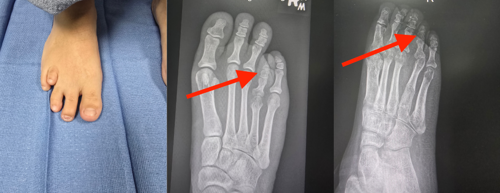

Johns Hopkins Aramco Healthcare (JHAH) has become the first hospital in the Eastern Province to offer routine corrective surgery for brachymetatarsia, a foot deformity that causes a patient’s toe to appear significantly shorter than the others.

Patients with brachymetatarsia have one or more metatarsals — bones in the middle of the foot — that are significantly shorter than the others. This makes one or more of their toes look unusually short. Brachymetatarsia is most common in the fourth metatarsal, which affects the toe next to the little toe.

To bring a patient’s toe into line with the others, a surgeon cuts the shortened metatarsal bone and attaches a device known as an external fixator. The patient is discharged the same day. While at home, the patient makes small adjustments to the fixator every few days to slowly lengthen the metatarsal bone.

After about 12 weeks, when the metatarsal has reached the desired length and the new bone has strengthened sufficiently, the patient visits the outpatient clinic to have the fixator removed. They can then walk out of the clinic wearing protective shoes, and within a few days, they are able to wear the footwear of their choice.